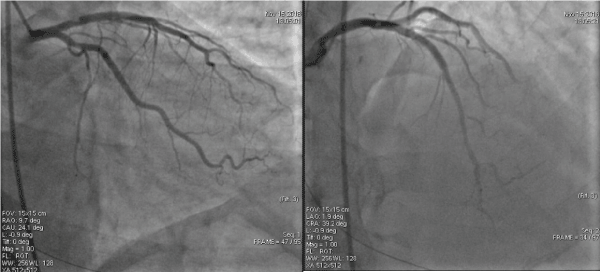

At the current presentation, coronary angiograms revealed filling defect at the proximal edge of the sirolimus-eluting stent (SES) (Figure 1). Optical coherence tomograms (OCT) of the LAD confirmed it as a red thrombus, overlying substantial exposed unendothelized stent struts. There was no proximal edge malapposition of the DES and no restenosis secondary to neoatherosclerosis in the mid segment; and undisrupted neointimal formation in the distal segment of the stent (Figure 2). Since the thrombus was non occlusive, the patient was started on GP IIb/IIIa inhibitors and heparin for 5 days. After 5 days of good anticoagulation, the patient underwent check angiography, which revealed that the proximal end of the stent was clear of the thrombus. OCT confirmed complete disappearance of the thrombus with the anticoagulation (Figure 3). The patient recovered uneventfully and was discharged from the hospital with dual anti platelets (aspirin and ticagrelor).

Figure 1. Coronary angiograms revealed filling defect at the proximal edge of the drug-eluting stent